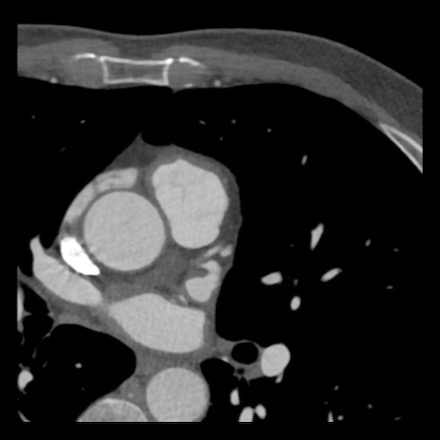

Same patient. First, study the CTA image.

The coronal image shows a central low-attenuation area around the lumen

of the LAD.

This low-attenuation area is surrounded by a higher attenuation

area.

This finding is the earlier discussed napkin-ring sign, which is a high-risk

plaque feature.

This patient classifies as CAD-RADS 4A/P1/HRP.